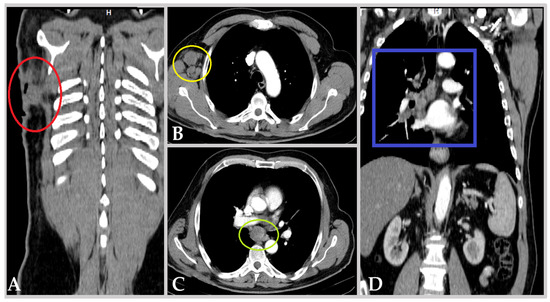

| Date | Procedure | Findings | Concomitant Treatment 1 |

|---|---|---|---|

| 12 July 2019 | TURBT | - pTaG2 high grade; - muscularis propria absent. | Dabrafenib + Trametinib |

| 2 June 2020 | TURBT | - pTaG2 high grade, but with residual tumor; - muscularis propria present. | Nivolumab |

| 9 July 2020 | TURBT | - pT1G2 high grade (biopsy), i.e., large residual tumor. | Nivolumab |

| 30 September 2020 | Cistoscopy | - complete spontaneous tumor necrosis. | Nivolumab |

| 1 February 2021 | TURBT | - pT1G2 high grade, with focal squamous features; - muscularis propria absent. | Nivolumab |

| 23 March 2021 | Radical Cystectomy | - pTaG2 high grade, “early urothelial carcinoma”, R0; - N0 (34 lymph nodes); - incidental prostatic adenocarcinoma, GS 3 + 3 = 6, pT2a | Nivolumab |